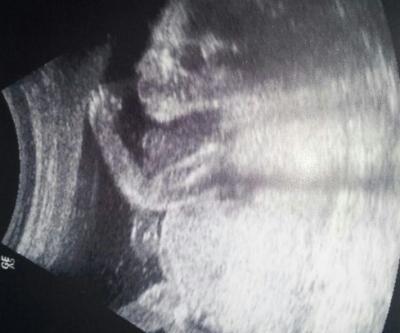

Huhu hab mich grad im juli bus Verfahren! ! Wollt nur wissen ob ihr anhand von meinem bild das Geschlecht erkennen könnt.

Also für mich sieht das schon wie ein Junge aus, trotz der Seitenlage blitzt da für mich was hoch ...

Für mich sieht das aus wie ein Junge !!!

Kann leider nichts erkennen, sorry. Aber das Bild ist süß! Sieht aus, als trinkt das Baby aus einer imaginären Flasche

Junge, ode vielleicht doch eine Nabelschnur ? Aber ich tippe auf junge , sieht für mich danach aus :-)